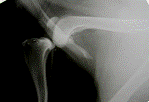

Рис.3. а - рентгенограмма коленного сустава собаки с разрывом ПКС; б - рентгенограмма коленного сустава собаки после проведения тройной остеотомии голени

Рис.4. Разрыв передней крестовидной связки (смещение центра мыщелков бедренной кости относительно центра плато большеберцовой кости). Уменьшение угла между осью диафиза большеберцовой кости и плато.

Рис.5. Стабилизация коленного сустава по методу ТОТ

Стабилизация коленного сустава происходит за счет увеличения угла между осью диафиза и плато большеберцовой кости, а так же за счет смещения бугристости большеберцовой кости, которая тянет прямую связку надколенника и коллатералные связки коленной чашки краниально, что так же способствует стабилизации коленного сустава.